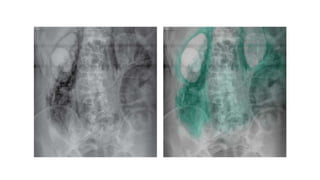

SPECIAL CASE : TOXIC

MEGACOLON

Acute form of bowel dilatation

occurring as a complication of IBD

or infection.

Rapid dilatation of colon and signs

of septic shock.

1. large bowel dilatation to >6cm

diameter

2. inflammatory pseudopoylps

(mucosal islands) – lobulated

opacities in the bowel wall from the

areas of raised mucosal tissue

surrounded by areas of ulceration.

3. thumb printing and mucosal

FAECAL LOADING